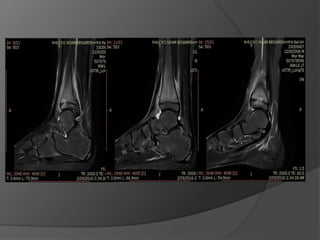

Case 1: A“healthy” 50 year old

Fell off a 3 ft high parapet

c/o pain, inability to bear weight on the right

foot

Initial radiographs

6 weeks later the cast was taken off, unable to bear

weight

Diagnosis

?

Lisfranc fracture- dislocation

Bony or ligamentous injury involving the tarsometatarsal